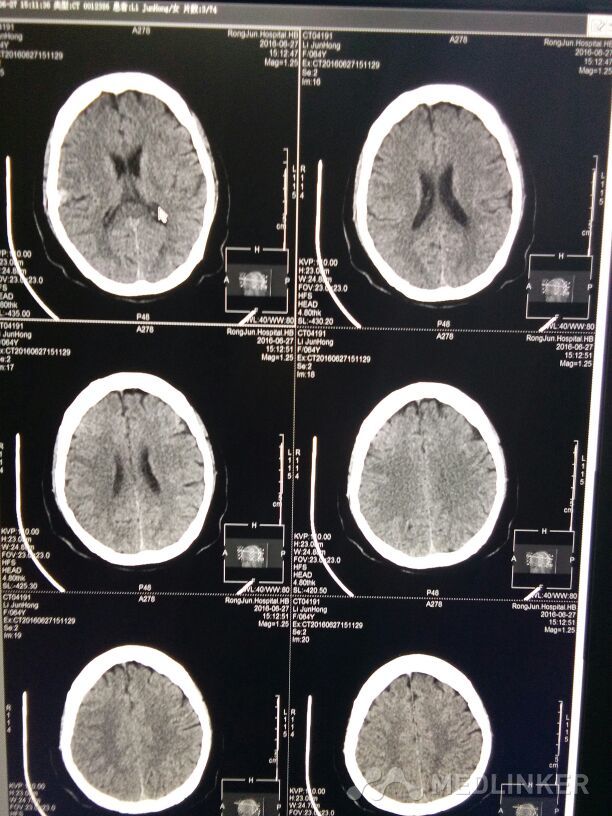

右颞叶脑膜瘤

所见:右颞叶可见一卵圆形稍高密度影,大小约1.2x1.9cm,边缘可见钙化,周围无明显水肿,余脑实质密度正常,脑室系统及脑沟,裂未见明显异常中线结构居中。 提示:右颞叶脑膜瘤。